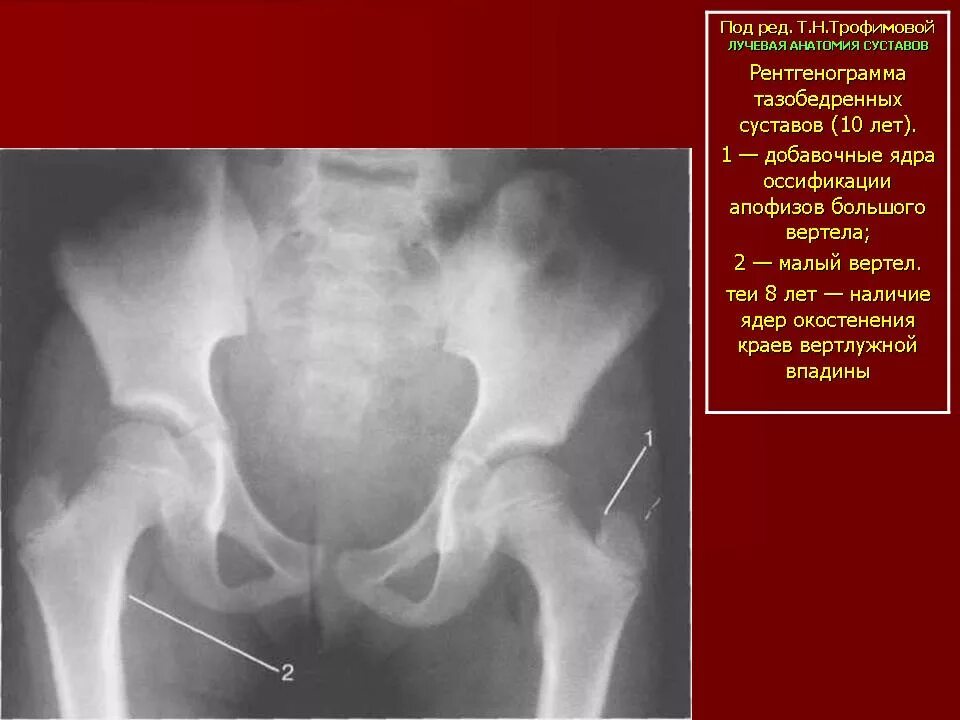

Ядро тазобедренного сустава